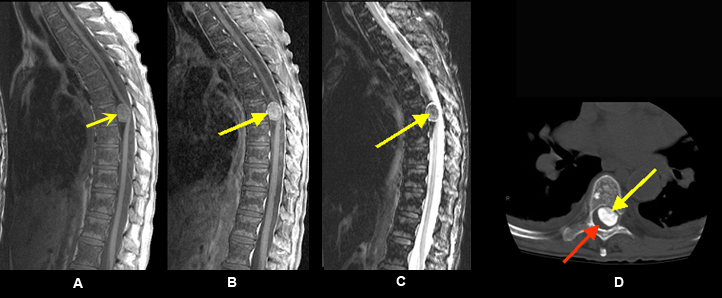

Imaging findings: Figure 4

- Pre-contrast sagittal T1wtd. MRI of cervical spine

- hypointense intradural mass (black arrow)

- Post-contrast (C+) sagittal T1wtd. MRI

- an enhancing intradural nerve sheath tumor (red arrow)

- Pre-contrast axial T1wtd. MRI

- hypointense dumbbell shape intradural mass (green arrow)

- Post-contrast axial T1wtd. MRI (C+)

- red arrow points to an enhancing intradural nerve sheath tumor

- yellow arrow points to cord compression

- green arrow points to the dumbbell shape of tumor with intraspinal component producing cord compression and paraspinal tumor extension through an enlarged neural foramen

Final impression:

- Dumbbell shape of tumor with intraspinal component producing cord compression and paraspinal tumor extension through an enlarged neural foramen following the exiting nerve root. This is characteristic of nerve sheath tumor.

- An enhancing intradural extramedullary nerve sheath tumor.

Imaging findings are consistent with schwannoma. |